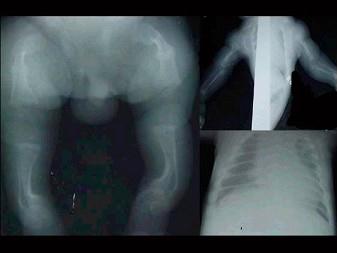

女,6个月,身体发育异常,眼巩膜呈蓝色,结合图像,最可能的诊断为?(?)A.成骨不全B.粘多糖病C.软骨发育不全D.佝偻病E.侏儒症

问题 女,6个月,身体发育异常,眼巩膜呈蓝色,结合图像,最可能的诊断为?(?)

选项 A.成骨不全 B.粘多糖病 C.软骨发育不全 D.佝偻病 E.侏儒症

答案 A